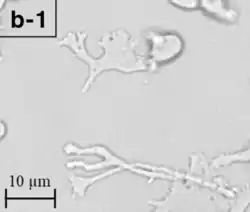

| Trophozoite (active) form of Balamuthia mandrillaris | |

B. mandrillaris is a free-living, heterotrophic amoeba, consisting of a standard complement of organelles surrounded by a three-layered cell wall (thought to be made of cellulose or a similar polysaccharide[8]), and with an abnormally large cell nucleus. On average, a Balamuthia trophozoite is about 30 to 120 μm in diameter. The cysts fall around this range, as well.[9]

Balamuthia's lifecycle, like the Acanthamoeba, consists of a cystic stage and a non-flagellated trophozoite stage, both of which are infectious, and both of which can be identified in the brain tissue on microscopic examination of brain biopsies performed on infected individuals. The trophozoite is pleomorphic and uninucleated, but binucleated forms are occasionally seen. Cysts are also uninucleated, possessing three walls: an outer thin irregular ectocyst, an inner thick endocyst, and a middle amorphous fibrillar mesocyst.[10]